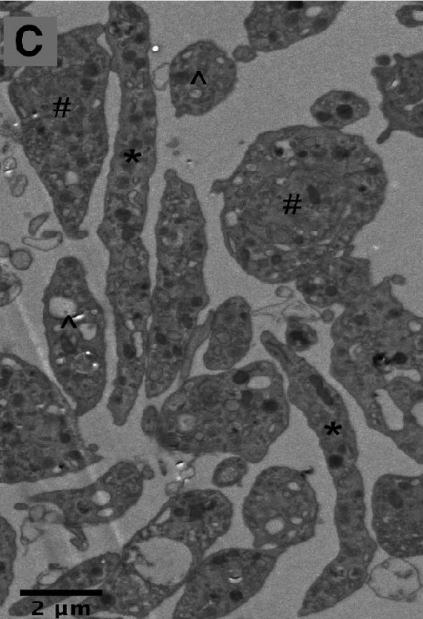

电子显微镜下的前血小板(#和*标注)与血小板(^标注) | 图源:Machlus K R, Italiano J E.新生成的前血小板会立刻穿过血窦壁进入血管内,其内的微管还会继续延伸,促使它们再次分裂,形成我们熟悉的血小板。